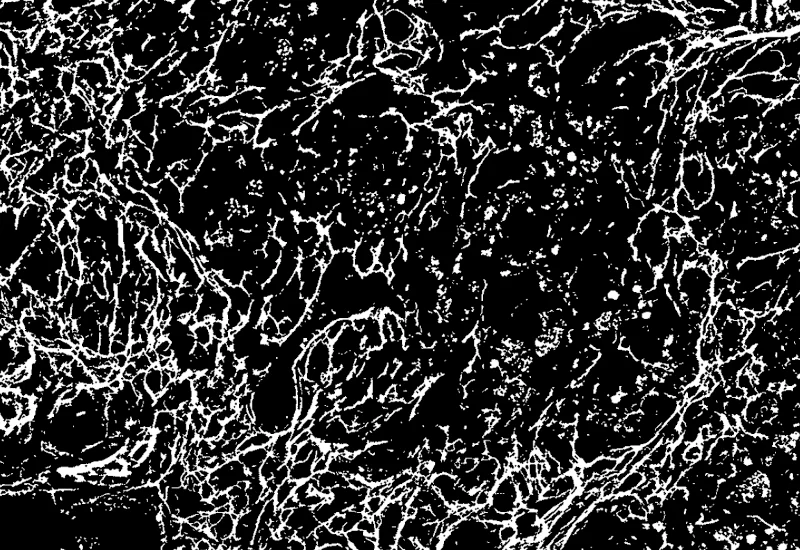

IHC Extracellular Filaments

Detect nuclei and extracellular filaments in IHC-stained sections, and quantify nuclei number, total filament area, and filament length.

The IHC Extracellular Filament App detects nuclei as well as extracellular filaments stained with specific markers. It outputs the number of nuclei, the total gilaments area and the lenght of the filaments.

Filament detection mask